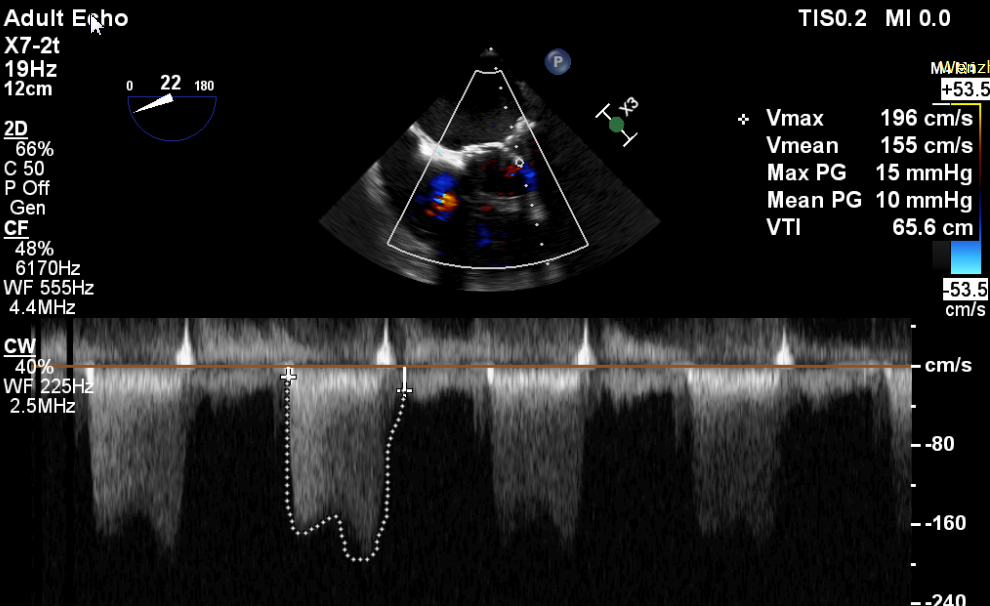

原生物瓣少量反流

过瓣流增快,呈“五彩状”

CDFI提示过瓣血流通畅

CDFI示少量瓣周漏